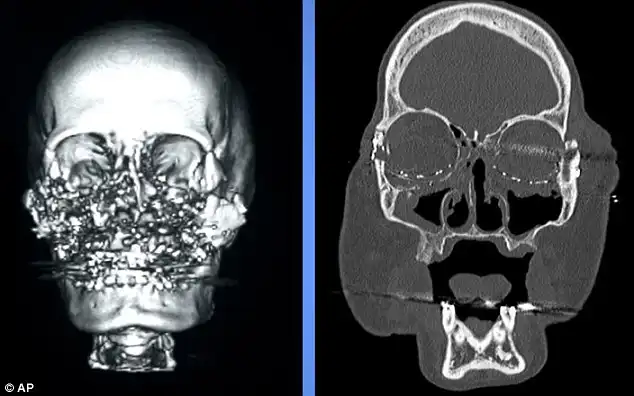

Так выглядел череп мисс Калп до операции, а так стал выглядеть после.